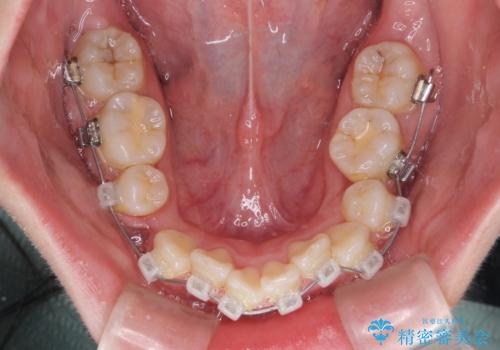

- 矯正装置

- クリアブラケット

気になっていた八重歯は装置装着から3か月ほどで解消されました。